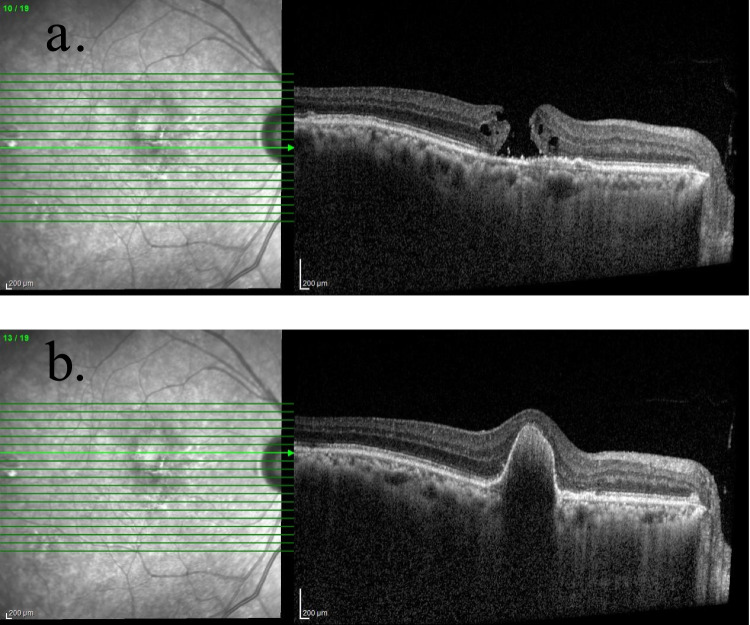

Patients and methods: A 63-year-old man with idiopathic PCV was treated with intravitreal faricimab. Although pigment epithelial detachment (PED) decreased, he developed cystoid macular edema with vitreomacular traction (VMT), which progressed to a FTMH.

Results: Pars plana vitrectomy and internal limiting membrane peeling successfully treated the FTMH. One year after the procedure, the macular hole remains closed, and the PCV was inactive.